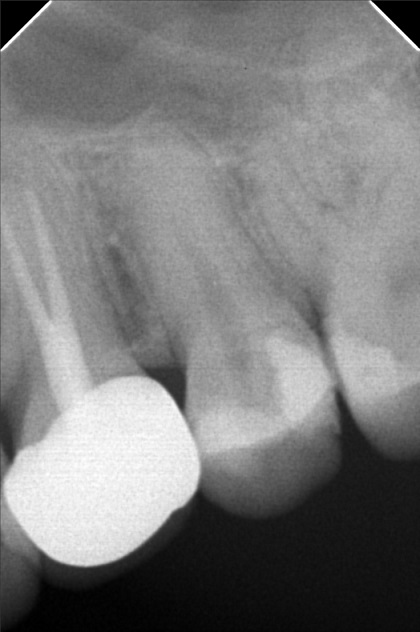

Edit Record Check our patient data records. Add patient information Patient Info Profile picture Last Name First Name Middle Name Birthdate Age Street Barangay City Country Zip Code Contact number Email Procedure 10/13/21- 26 LC with MTA MOD 23 Lingual Distal 11/24/21 - 25/27 LC# 27 #15 IRM -/Xray 03/16/22- zircinia prep on 15/16 shade: a3 body, cervical b3 digital impression done temporary crown done LC mesial 15, distal 14 xray on 24 3/25/22- installation 15, 16 zirconia opening of canal 24 TF with EUgenol 03/30/22 Lingual 18/ Buccal 19 Formocresol Incision and drainage Laser rx: co amoxiclav 625 mg/ mefenamic 500 mg 04/29/22- lingual 16.5mm buccal 19mm 05/04/22- obturation/ LC 8/12/22 - tooth prep #24 8/18/22- Cementation zirconia crown #24 8/26/22 - xray, intraoral radiograph 05/12/23- OP(L) 05/19/23- Xray/ Ozone/Resto - #21(mesial & lingual) 09/10/24 OP w/ air polisher 07/19/25 op with air polisher + fluoride 03/18/26 OP 04/08/26 #48 - Occ mesial MTA Fiber Biomimetic File delprado26.jpg File 2 delprado23-24-25.jpg File 3 6afb059c-2de8-4dc8-ac4d-ae6435b6dabc.jpeg File 4 katherine_del_prado.jpg File 5 katherine_del_prado_02.jpg File 6 katherine_del_prado_03.jpg File 7 File 8 File 9 File 10 File 11 File 12 File 13 File 14 File 15 File 16 File 17 File 18 File 19 File 20 Retain Record Retain Record Yes No Save Your Changes